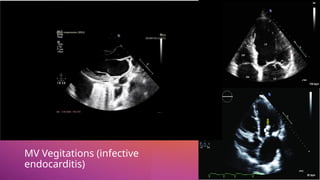

Infective

Endocarditis

• Infective endocarditis with leaflet

vegetation and fenestration (Carpentier

Type I) is an important cause of primary

MR associated with significant morbidity

and mortality.

• The mechanism of MR with infective

endocarditis is initially an inflammation of

the valve leaflets causing a valvulitis, which

is seen as nonspecific thickening on

echocardiography, although in many cases,

thickening is not evident.

• Valvulitis results in inefficient or incomplete

coaptation of the leaflets and MR.

• As the inflammatory response

progresses, valve tissue is destroyed

and vegetation forms on the valve

leaflets. The destruction of valve tissue,

often signaled by the development of

vegetation, may also result in MR

MV Vegitations (infective

endocarditis)

MV Vegitations

(infective